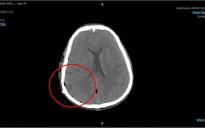

Trước khi nhập viện, bệnh nhân nam (35 tuổi) đột ngột đau đầu, nôn ói. Bệnh nhân được chuyển đến bệnh viện trong tình trạng xuất huyết lấp đầy toàn bộ hệ thống não thất. Tình trạng này gây bít tắc đường lưu thông của dịch não tủy, làm tăng áp lực nội sọ nghiêm trọng, đe dọa trực tiếp tính mạng của bệnh nhân.

BS Võ Doãn Tiến, Khoa ngoại Thần kinh - Cột sống - Bệnh viện Đa khoa Quốc tế Minh Anh, cho biết kết quả chụp CT-Scan dựng hình mạch máu não (CTA) cho thấy tình trạng hẹp rất nặng ở đoạn cuối của động mạch cảnh trong hai bên, có hình ảnh điển hình của bệnh lý Moyamoya. Đây là một bệnh lý hiếm gặp.

Khi não bị thiếu máu, cơ thể sẽ phản ứng bằng cách tự tạo ra các mạch máu nhỏ, li ti, mỏng manh giống như "làn khói" để cố gắng bù trừ. Chính những mạch máu "tân tạo" này lại có thành mạch rất yếu, rất dễ vỡ. Ở bệnh nhân này, các mạch máu mỏng manh đó đã vỡ ra, gây nên tình trạng xuất huyết não nghiêm trọng.